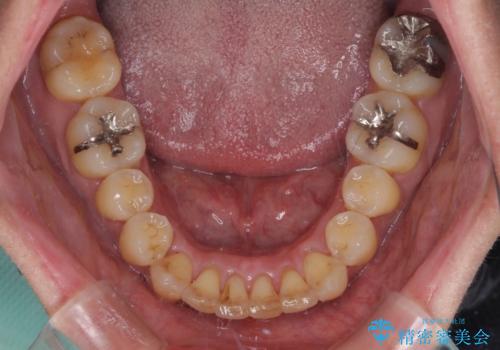

- 前歯のデコボコを気にして来院された患者様です。

インビザラインまたはワイヤー装置、どちらでも対応可能でしたが、自己管理の少なさ、期間の短さから、ワイヤー装置による矯正治療を行うこととしました。